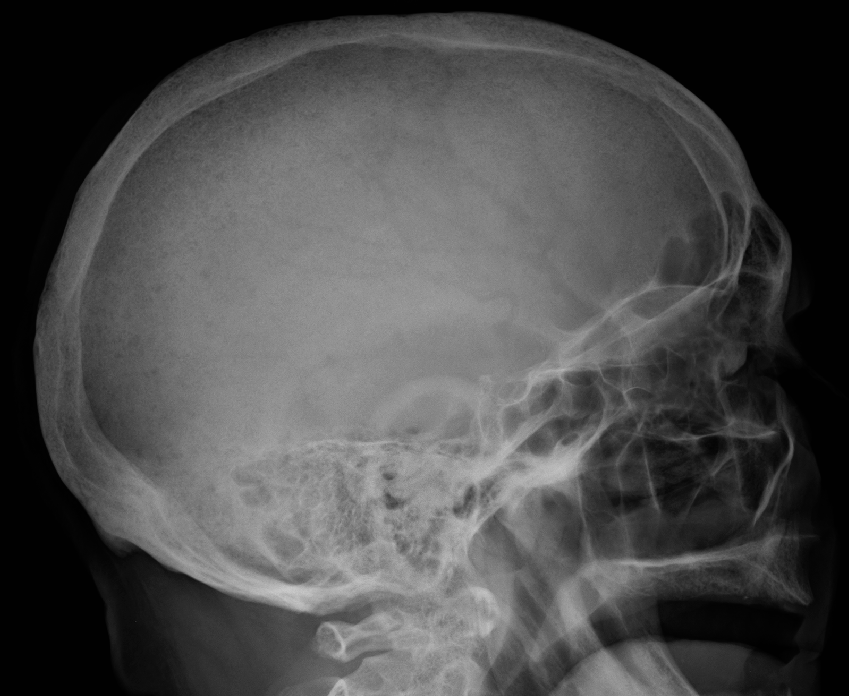

Το πολλαπλό μυέλωμα μπορεί να ανιχνευθεί κατά τη διάρκεια μιας αιματολογικής εξέτασης ρουτίνας, ωστόσο το πιθανότερο είναι να διαγνωσθεί μόνο μετά από ακτινογραφίες οστών λόγω καταγμάτων ή γιατί οι ασθενείς παρουσιάζουν άλλα συμπτώματα. Τα συμπτώματα είναι δυνατό να ποικίλουν από άτομο σε άτομο. Ορισμένοι άνθρωποι δεν παρουσιάζουν συμπτώματα κατά τη διάρκεια των πρώιμων σταδίων της νόσου. Κοινά συμπτώματα περιλαμβάνουν:

– Οστική βλάβη, συμπεριλαμβανομένων καταγμάτων και/ή λέπτυνσης των οστών

Η διάγνωση του πολλαπλού μυελώματος καθορίζεται από τα αποτελέσματα των παρακάτω εξετάσεων:

– Μαγνητική τομογραφία ή ακτινογραφίες για τον έλεγχο πιθανής λέπτυνσης των οστών ή καταγμάτων